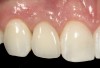

Fig 1. Midfacial recession can affect the esthetics of a smile and lead to an unsatisfactory outcome.

Fig 2. The cause for midfacial recession is excessive labial implant placement. Secondary to poor placement is overcontouring of the implant abutment.

Problem: The implant is placed too facial with significant recession on the midfacial aspect of the abutment and/or crown; the implant is healthy and the patient has a high smile line with an intermediate to thick periodontal phenotype (Figure 1 and Figure 2).17-19